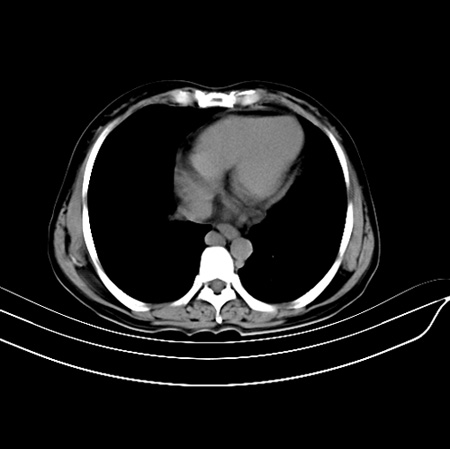

以下是引用江尾海头在2007-9-7 19:01:00的发言:[br]肝叶比例失调,肝边缘高低不平,尾状叶增大,肝裂增宽。肝右叶见较大密度减低影,边缘欠清。脾脏明显增大,胃底及奇静脉半奇静脉曲张。胆囊未见明显显示。 考虑:1、肝癌。2、肝硬化伴脾大静脉曲张。

以下是引用zhangxu5888在2007-9-7 22:31:00的发言:[br]1、肝硬化,食管 胃底及奇静脉半奇静脉曲张;2、脾脏肿大; 3、肝右叶的病灶呈锲性改变,内可见条片状钙化,边界清晰,密度明显低于周围正常肝组织,我觉得肝癌可能性不是很大, 同意楼上观点,有可能是栓塞,建议增强.